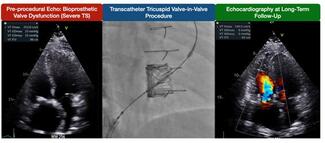

The authors sought to determine the long-term clinical and hemodynamic outcomes of patients undergoing transcatheter valve-in-valve tricuspid procedures.